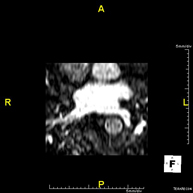

- Intracranial MRI angiography

This non-invasive diagnostic procedure uses an electromagnetic field and radio waves (from a transmitter and receiver) to acquire high-definition anatomical images of the cerebral arteries. It is a radiation-free procedure. In most cases, paramagnetic contrast (gadolinium) is required. It enables non-invasive angiographic studies using a gadolinium injection, with subsequent 2D and 3D reconstruction using specialised workstations. Indicated for: Vascular malformations, cerebral artery aneurysms, arteriosclerosis.